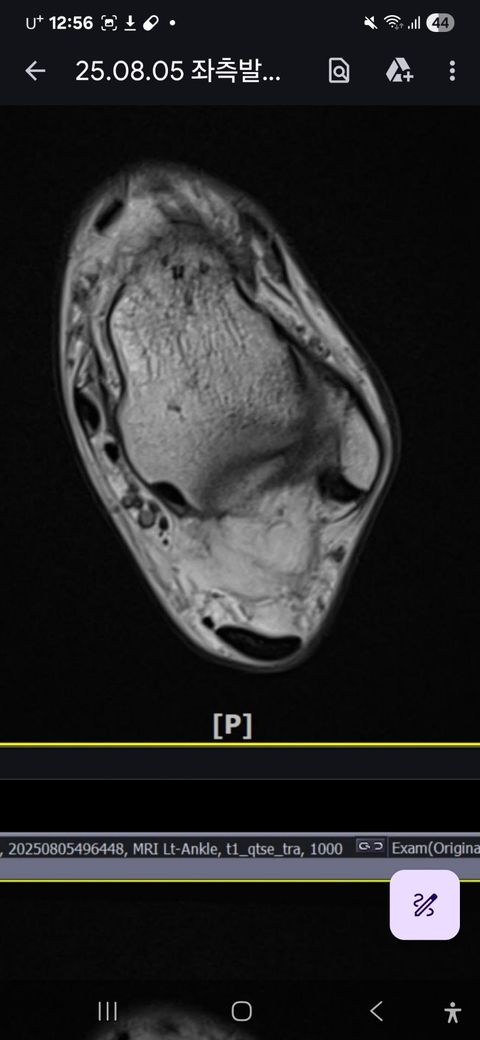

발목인대 상태 질문드립니다. (mri사진 첨부)

그런데 다친 지 2주 뒤부터 발목이 쑤시듯 아파 병원에서 초음파 검사를 했고, 전거비인대(ATFL) 2도 염좌 진단을 받았습니다. 이후 약 6주 동안 주 1회씩 충격파, 물리치료, 도수치료 등을 받았습니다. (고정치료는 시기가 늦었다며 진행하지 않았습니다.)

그래도 통증이 남아 8월 5일에 MRI를 촬영했는데, 병원에서는 “인대는 이어져 있고, 이 정도면 재활운동으로 호전될 것”이라는 설명을 들었습니다.

MRI 상 전거비인대와 발목 상태가 정말 회복 단계인지, 아니면 만성으로 넘어가는 건 아닌지 전문가분들의

의견을 듣고 싶습니다.

• 2번 째 사진

올려주신 mri를 보면 전거비인대는 연속성이 유지되고 있고 파열이나 큰 손상 흔적은 없어 재활로 회복 가능한 상태로 보입니다 다만 3개월 가까이 활동 시 통증과 미열감이 남아 있는 것은 조직 회복이 아직 완전히 끝나지 않았거나 주변 연부조직 관절 움직임 제한 등으로 인한 과민 반응일 수 있습니다.

초음파와 비교하면 mri 상으로 인대 연속성이 확인되므로 심각한 악화나 재파열은 아닌 것으로 판단됩니다